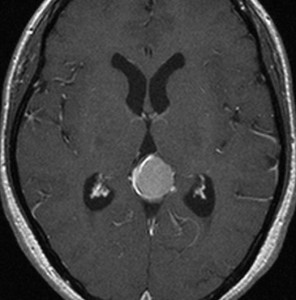

若い女性に偶然発見されたものです。直静脈洞と静脈洞交会の接合部あたりに発生したもので,静脈洞はほぼ閉塞に近い所見でした。しかし,この部分の静脈洞は,テント硬静脈側副路が発達することがあるので,硬膜を含めた積極的な摘出をすることは絶対にできません。もしほんの少しでも流れがある直静脈洞を閉塞させると短時間に脳死になるような脳静脈圧亢進が生じる可能性があるからです。静脈洞内に少し取り残して(右下の矢印)手術を終了しました。手術後には定位放射線治療を行って再増大を防ぎます,